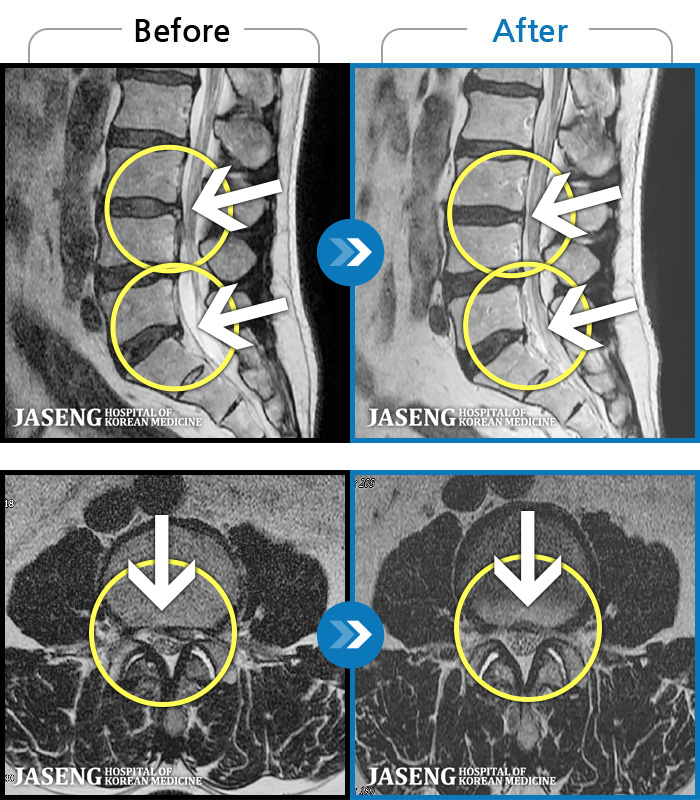

[뱸] 19.11.28~25.05.06